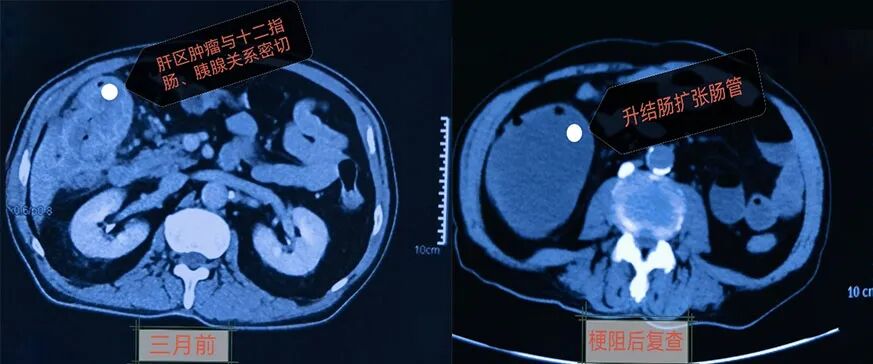

经多方了解,患者及家属慕名来到河北一洲肿瘤医院就诊。入院后,完善相关检查,既往结肠镜及腹部增强CT提示升结肠肝曲区及降结肠存在双原发肿瘤的可能。

结合影像学检查,考虑双原发结肠癌合并急性肠梗阻,肠腔压力持续升高,随时可能发生肠穿孔、感染性休克,病情十分危急。

影像检查结果

升结肠肝曲区存在巨大肿瘤,完全闭塞肠腔

肿瘤外侵明显,与十二指肠、胰腺形成致密粘连

同时合并降结肠肿瘤